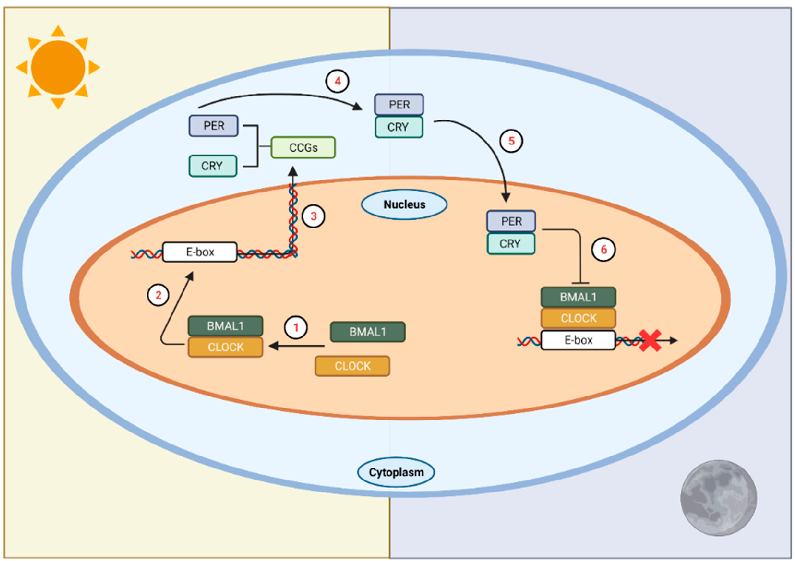

Circadian rhythm regulation involves a complex interplay between the central clock in the suprachiasmatic nuclei and peripheral oscillators throughout the body. Melatonin serves as the primary hormonal signal conveying darkness information to these systems.

Exogenous melatonin administration influences circadian phase positioning, with the direction and magnitude of phase shifts depending on the timing of administration. Evening doses advance the circadian clock, while morning doses may cause phase delays.

Clinical applications of melatonin extend beyond sleep induction to include circadian rhythm resynchronization in jet lag, shift work disorder, and delayed sleep-wake phase disorder. Dose-response relationships vary across these conditions.